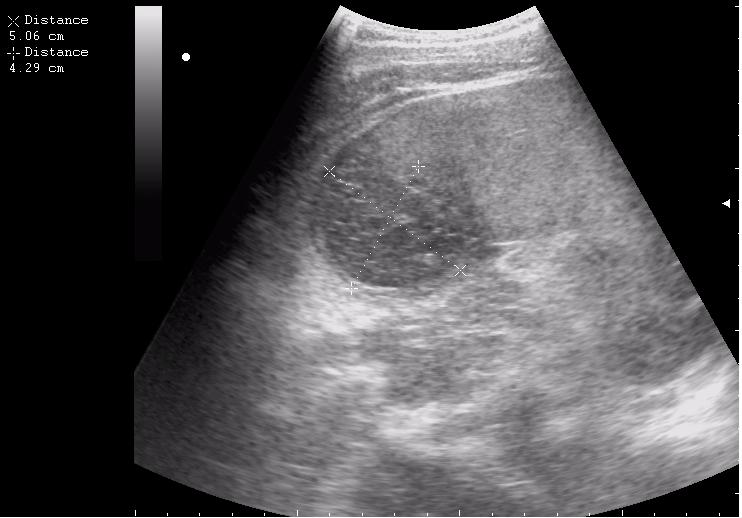

наезд большой черной Прады на маленькую (13кг) 5-летнюю девочку.

получает Медаксон, рабочая версия - изменение желчного пузыря вследствии травмы (шепотом - рекомендация хирургу сменить антибиотик)